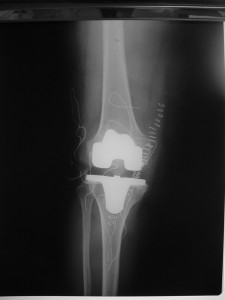

Total Diz Protezi

Total Diz Protezi ameliyatı 50 yılı aşkın bir süredir tüm dünya üzerinde bir çok farklı merkezde başarı ile uygulanmaktadır. Daha önceki yıllarda bu protezlerin ömürleri 10-15 yıl olarak bilinmekteyken, artık gelişen implant teknolojisi, artan bilgi paylaşımı ve ameliyat teknikleri ile bu yıl çok daha üst seviyelere çekilmiştir.

Total diz protezi (TDP) primer olarak dizde ciddi ağrıya neden olan artritli ( halk arasında diz kireçlemesi olarak bilinir) hastalarda endikedir. Özellikle ağrı ve dizde fonksiyon bozukluğu hastaların yaşam kalitesinde ciddi bozulmalara sebep olmaktadır. Hastaların bu ameliyatı olmadan önce konservatif tedavilerin tümünden fayda görmemiş olması gerekmektedir.

Bu ameliyat sıklıkla ileri yaştaki hastalara yapılmakla birlikte, romatolojik ve travmatik nedenlerle eklem fonksiyonları bozulan genç hastalara da başarı ile uygulanabilmektedir.

Ameliyat sonrası ilk 24 saatten sonra hemen mobilizasyon arzulanmaktadır. Ameliyatdan sonra 15. günde dikişler alınmakta ve normal yaşama dönme beklenilmektedir. Bu ameliyatdan sonra olabilecek en önemli komplikasyon erken dönemde tromboemboli atağı ve enfeksiyon iken geç dönemde implantta yetmezlik gelişmesidir. Bu kompikasyonlar ise son derece azdır.

Total Diz Protez ameliyatı kliniğimizde endikasyon dahiline her yaşa başarı ile uygulanmaktadır. Örnek olgumuz: